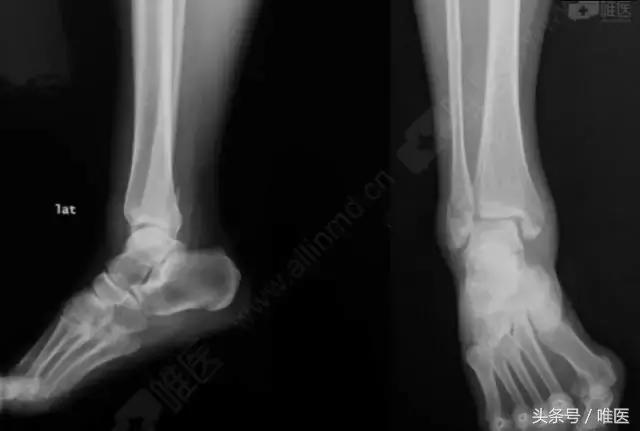

X线:右侧踝关节骨折

L-H分型:旋后外旋型 IV度;

Danis-Webber分型:B型

治疗前影像